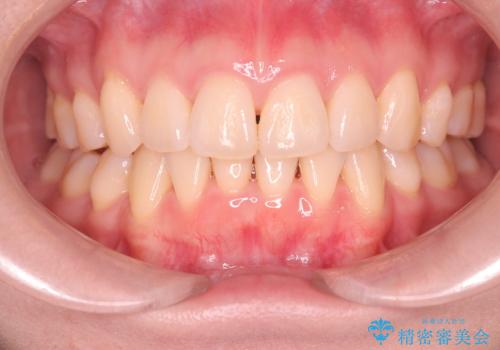

【審美ワイヤー】奥歯のガタガタを治したい

- 20代男性

- 治療期間

- 3年

- 歯並びの凸凹を主訴に来院されました。

スペースが必要なため、抜歯を行なって治療を行いました。

奥歯の捻れが強く治療期間がかかりましたが、綺麗な仕上がりに満足していただきました。